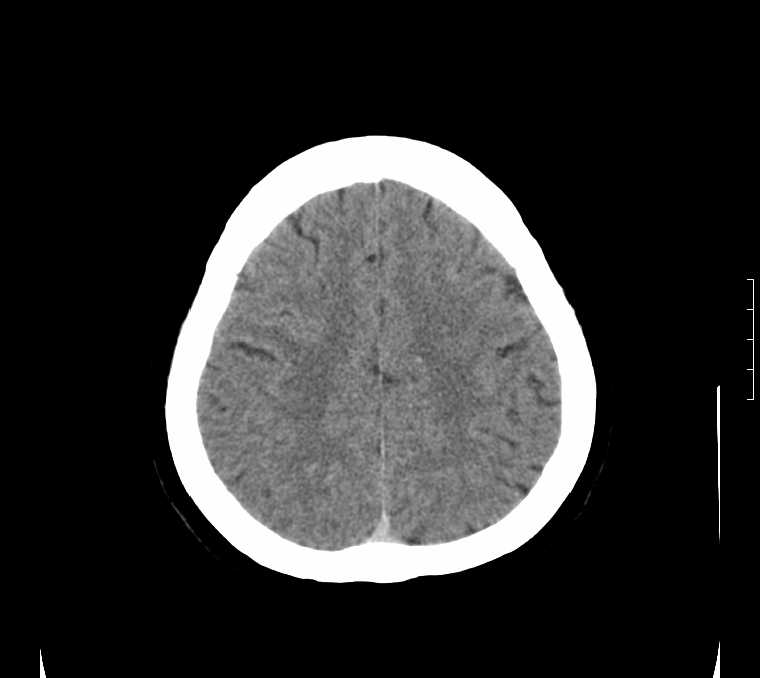

标题: CT24387:看看这例脑部改变!!

老年女性。头晕。

鉴别于特发性家族性脑血管亚铁钙沉着症(fahr`s病)与甲状旁腺机能低下之间,请结合临床及相关实验室检查。